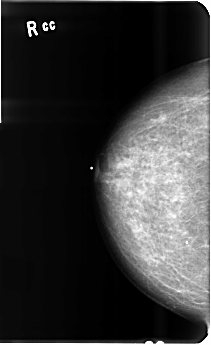

B_3512_1.RIGHT_CC

RIGHT_CC LINES 4824 PIXELS_PER_LINE 2952 BITS_PER_PIXEL 12 RESOLUTION 50 NON_OVERLAY